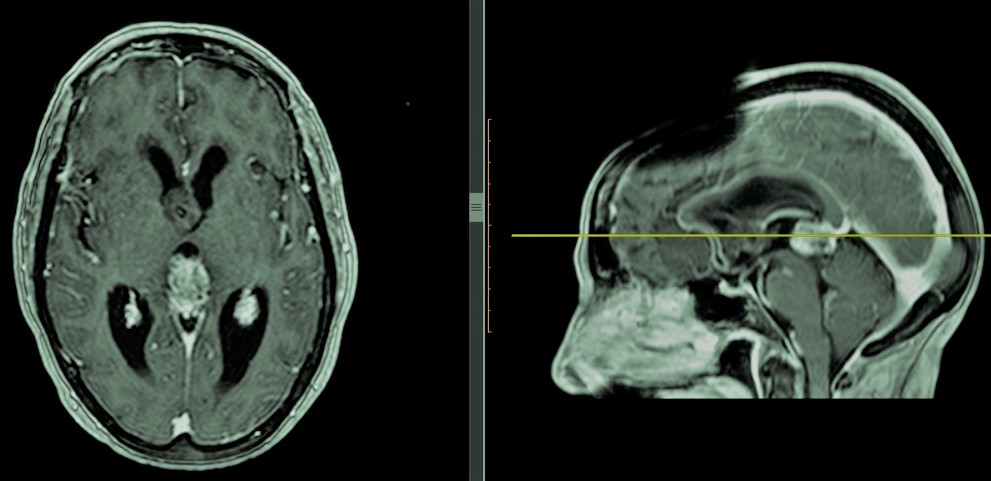

-Tumores pineales: Tienen lugar en la glándula pineal o epífisis situada en la parte posterior del diencéfalo y relacionada con la producción de melatonina y con los ciclos de sueño-vigilia. Al igual que sucede con los craneofaringiomas, los tumores pineales aunque típicos en niños, tienen lugar también en adultos. Existen una gran variedad de estirpes de tumores pineales que pueden exhibir grados de agresividad muy variados. En niños los más frecuentes son de tipo germinal (germinomas, sobre todo, y menos frecuentes coriocarcionas, carcinomas embrionarios, tumor de seno endodérmico y teratomas maduros/inmaduros), mientras que en adultos suelen tratarse de gliomas o meningiomas. Estos tumores suelen manifestarse con el llamado Síndrome de Parinaud, una incapacidad para dirigir la mirada hacia arriba en ocasiones acompañada de hidrocefalia obstructiva aguda e hipertensión intracraneal. En estos casos además de llevar a cabo cirugía sobre el tumor puede ser preciso una intervención previa para el tratamiento de la hidrocefalia. La necesidad de tratamiento con quimio o radioterapia está determinado, al igual que el pronóstico, por la estirpe del tumor.